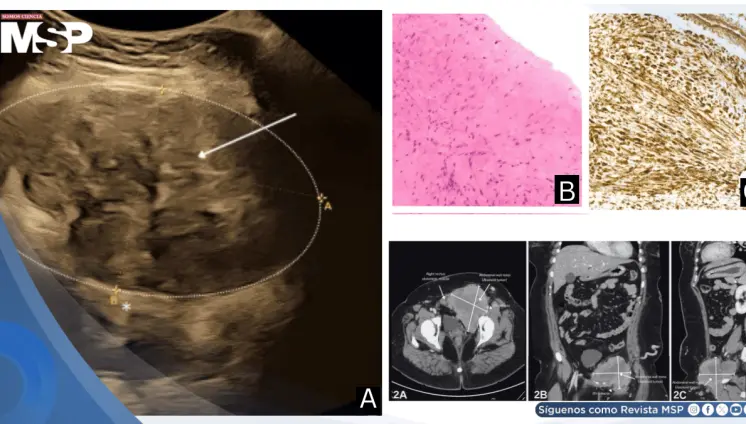

Masa rectal con tejido óseo y cerebral en mujer gestante es causada por un teratoma rectal maduro